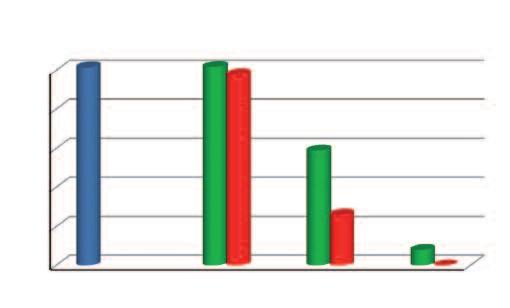

Demistificazione del cancro tramite le statistiche dell’OGM (Organizzazione Mondiale della Sanità)

Altre malattie

Malattie cardiocircolatorie

A. Ogni anno muoiono di cancro 7,5 milioni di persone

Altre malattie Infezioni Infezioni

Malattie cardiocircolatorie

B. Solo in Nord America e in Europa ogni anno muoiono di cancro 5,6 milioni di persone

All'inizio del XXI secolo, il cancro resta una dei più grandi flagelli del genere umano. E' quasi impossibile dimostrare la grandezza di questa epidemia. Per visualizzare le dimensioni di questo fenomeno possiamo prendere il totale annuale dei morti per cancro e confrontarlo con la popolazione delle principali città del mondo.

Ogni anno il cancro causa il decesso di 7,5 milioni di pazienti in tutto il mondo Come termine paragone, ecco le popolazioni di alcune delle più grandi metropoli del mondo: Tokyo 8,9 milioni di abitanti, Città del Messico 8,9 milioni, New York 8,4 milioni, Lagos (Nigeria) 8 milioni, Londra 7,8 milioni, Lima (Perù) 7,6 milioni, Hong Kong 7 milioni, Bangkok (Thailandia) 7 milioni, Il Cairo (Egitto) 6,8 milioni e Rio de Janeiro (Brasile) 6,3 milioni.

Aumento del numero dei decessi dovuti al cancro nei diversi gruppi di età, dal 1970 al 2000

Età dei pazienti 70 - 79 anni

Età dei pazienti 60 - 69 anni

Età dei pazienti 50 - 59 anni

Dati statistici per gli USA, dati comparabili per l’Europa. Fonte: Journal of the American Medical Association, 2005